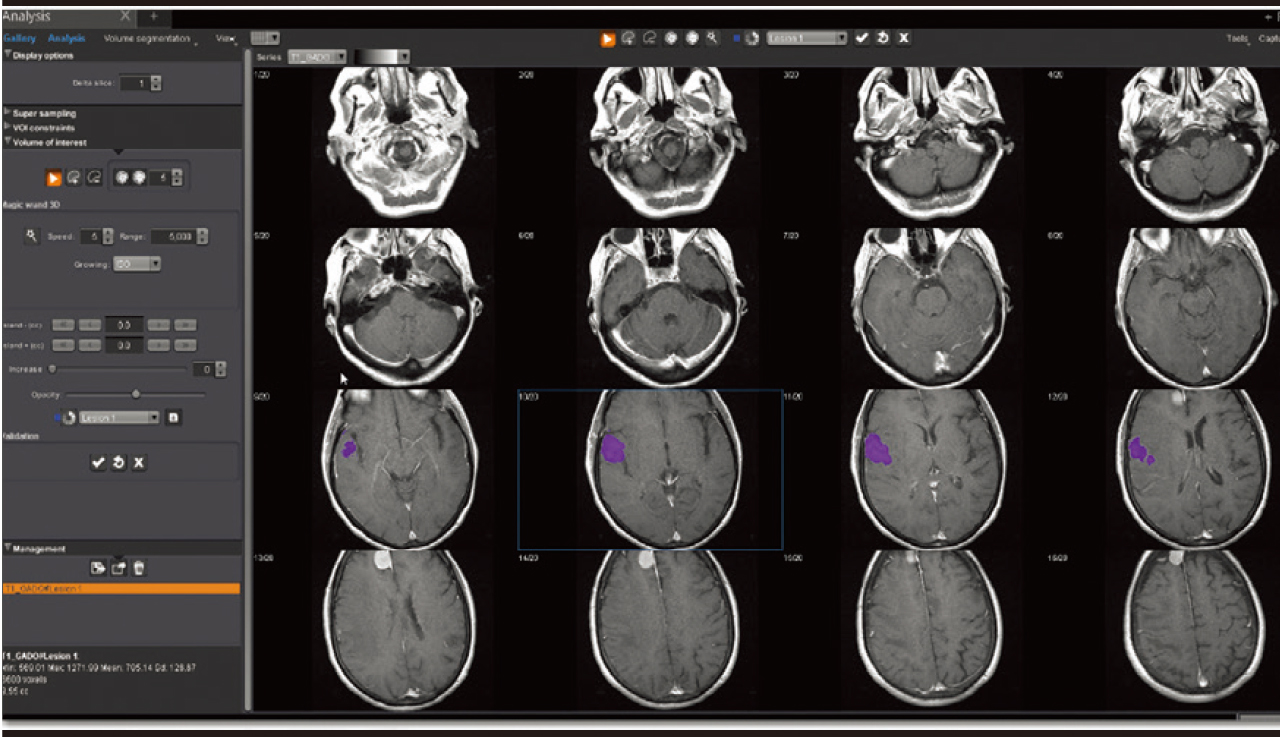

Аналіз

Додаток Аналіз візуалізує, сегментує, вимірює та оцінює широкий спектр наборів даних від звичайних серій до перфузійних та кінетичних серій разом із серіями DTI та DWI. Він забезпечує визначені користувачем накладання, включаючи візуалізацію органу/або патології, аналіз кінетики та кривих, аналіз кривих, статистику, співвідношення та гістограми, синтез декількох серій, напівавтоматичне сегментування об’єму, рендеринг об’єму та подальші динамічні спостереження.